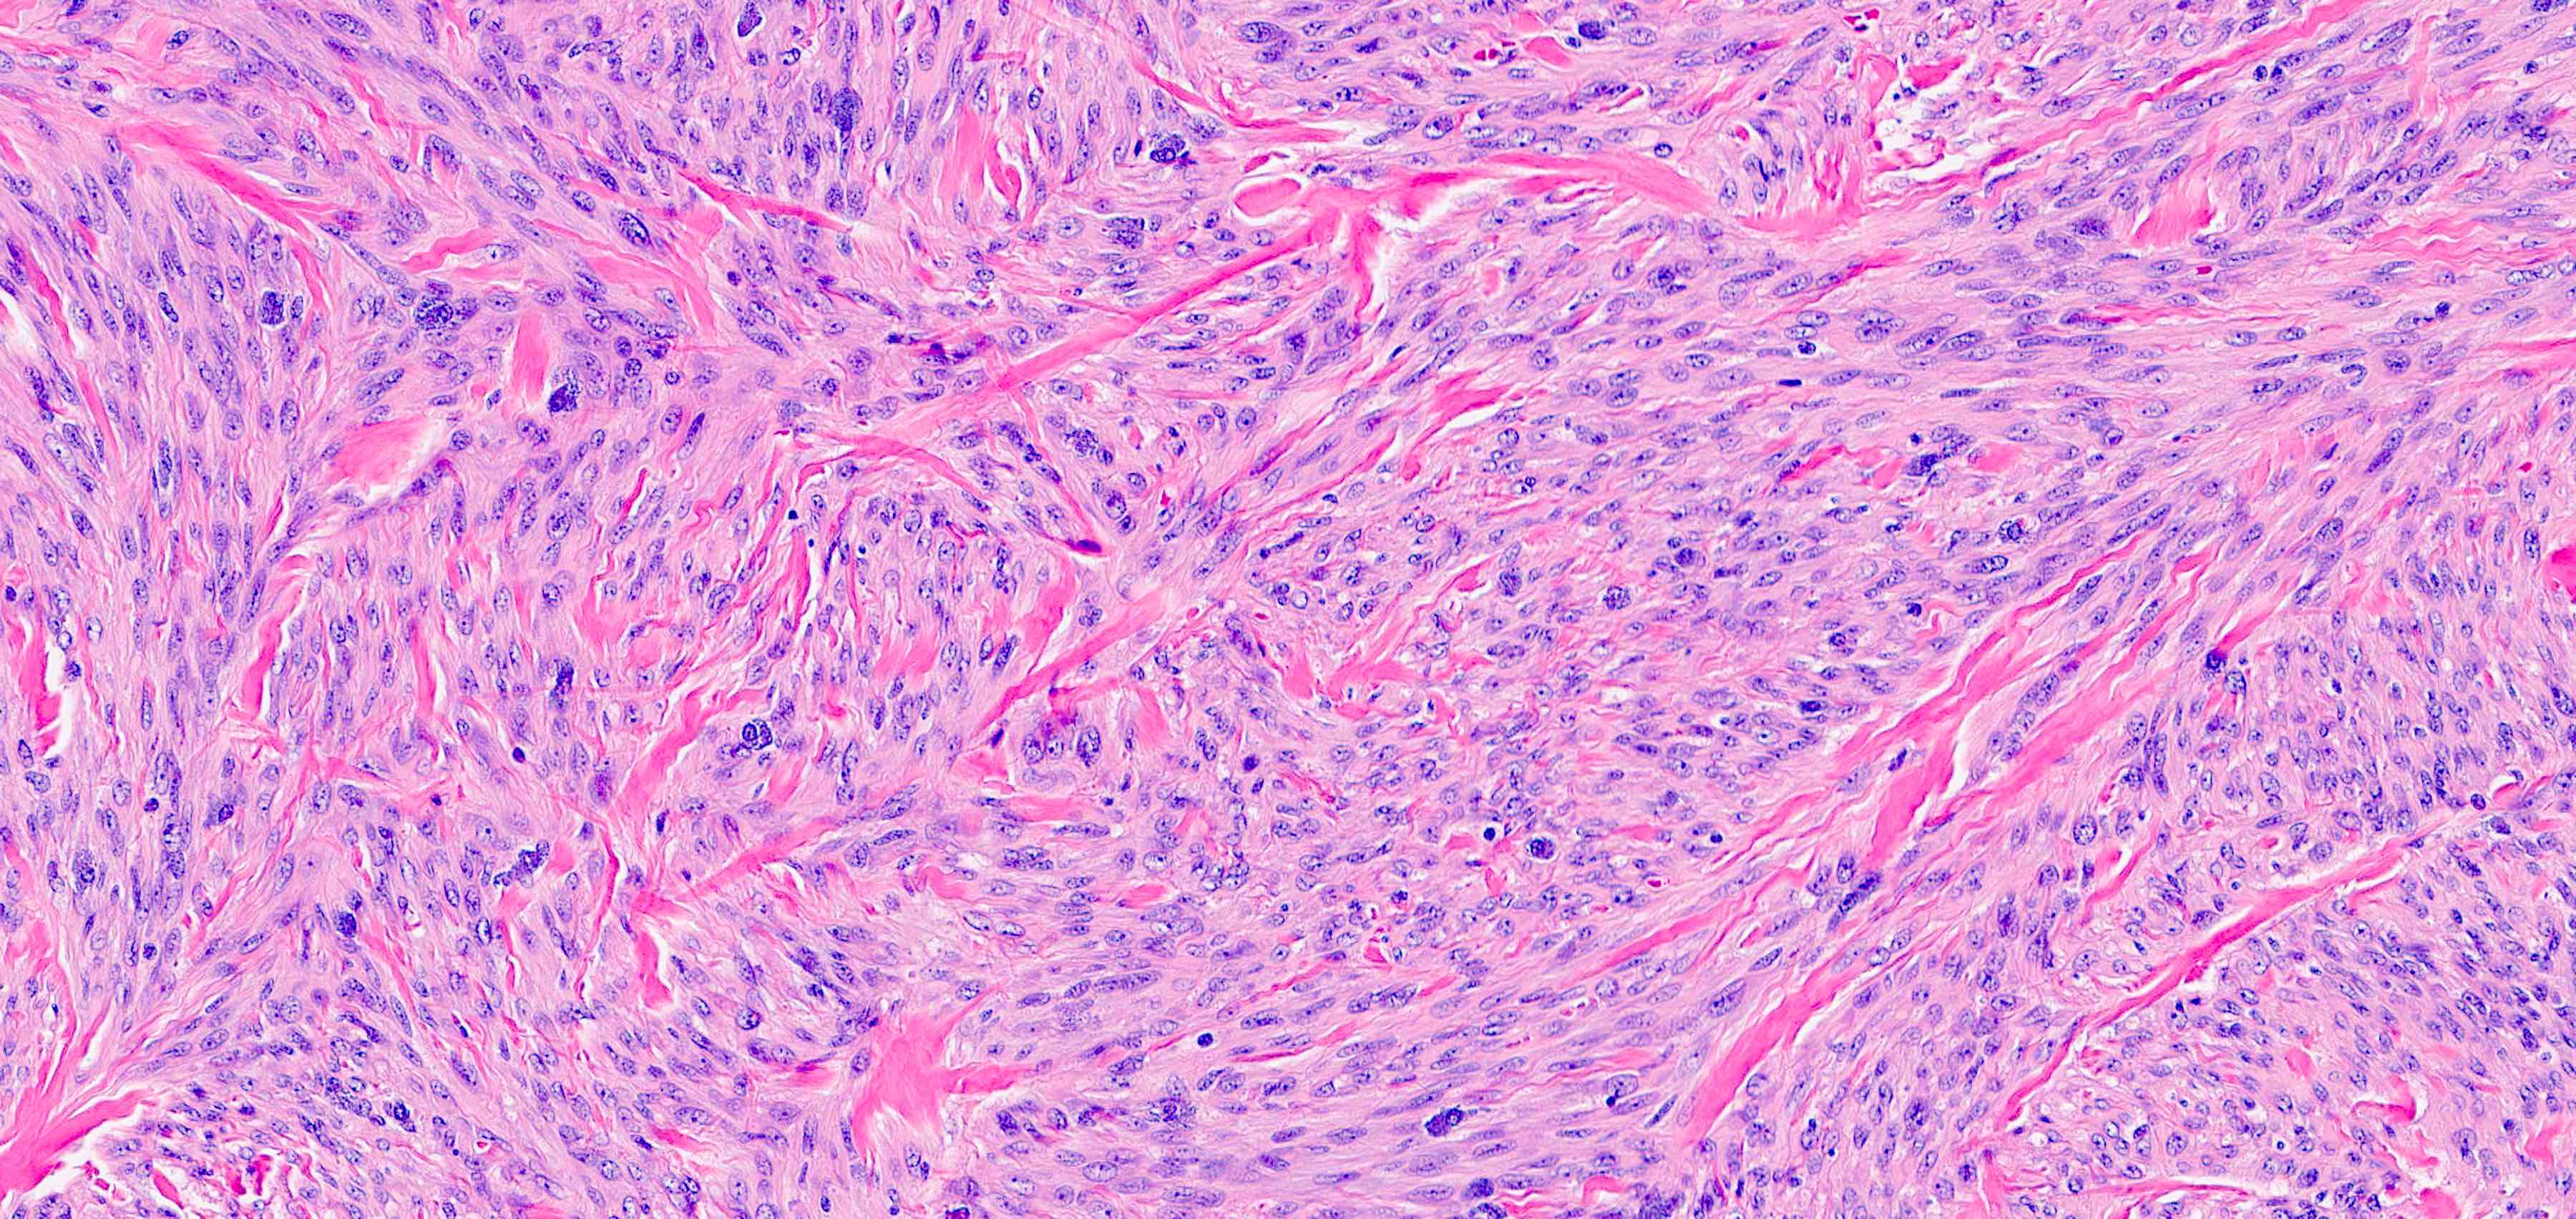

Microscopic (histologic) images

- Cellular: dense proliferation of myofibroblasts, ratio of spindle cells to collagen increased compared with classical variant, may have infiltrative borders, storiform or herringbone arrangement

- Bland, uniform, short to elongated spindle cells arranged as short haphazard intersecting fascicles admixed with bands of hyalinized, brightly eosinophilic collagen and variable amounts of fat

- No more than mild nuclear atypia

- Mitoses usually absent, atypical mitoses and necrosis absent

- Mast cells common, perivascular lymphocytic infiltrates on occasion